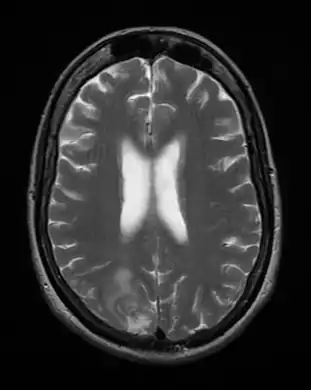

Cerebral toxoplasmosis (with primary involvement in the right occipital lobe)

Cerebral toxoplasmosis